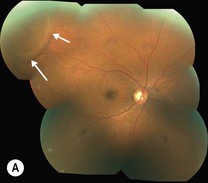

Senile retinoschisis is usually bilateral, with a smooth, domed appearance and most commonly develops inferotemporally (Fig. 25.1.1). There may be non-inflammatory sheathing of retinal blood vessels and retinal ‘snowflakes’ seen over the inner wall of the schisis cavity. An absolute scotoma is seen on visual field testing, in contrast to the relative scotoma seen in acute rhegmatogenous retinal detachment. Both inner and outer retinal breaks may be seen, but rarely in conjunction. Unlike a retinal detachment, no demarcation line is seen, unless the schisis progresses into a combined detachment.

Figure 25.1.1 Fundus photograph of a patient with peripheral retinoschisis (arrows), (A), and one with macular schisis, (B), Note the characteristic cartwheel appearance of the macula.